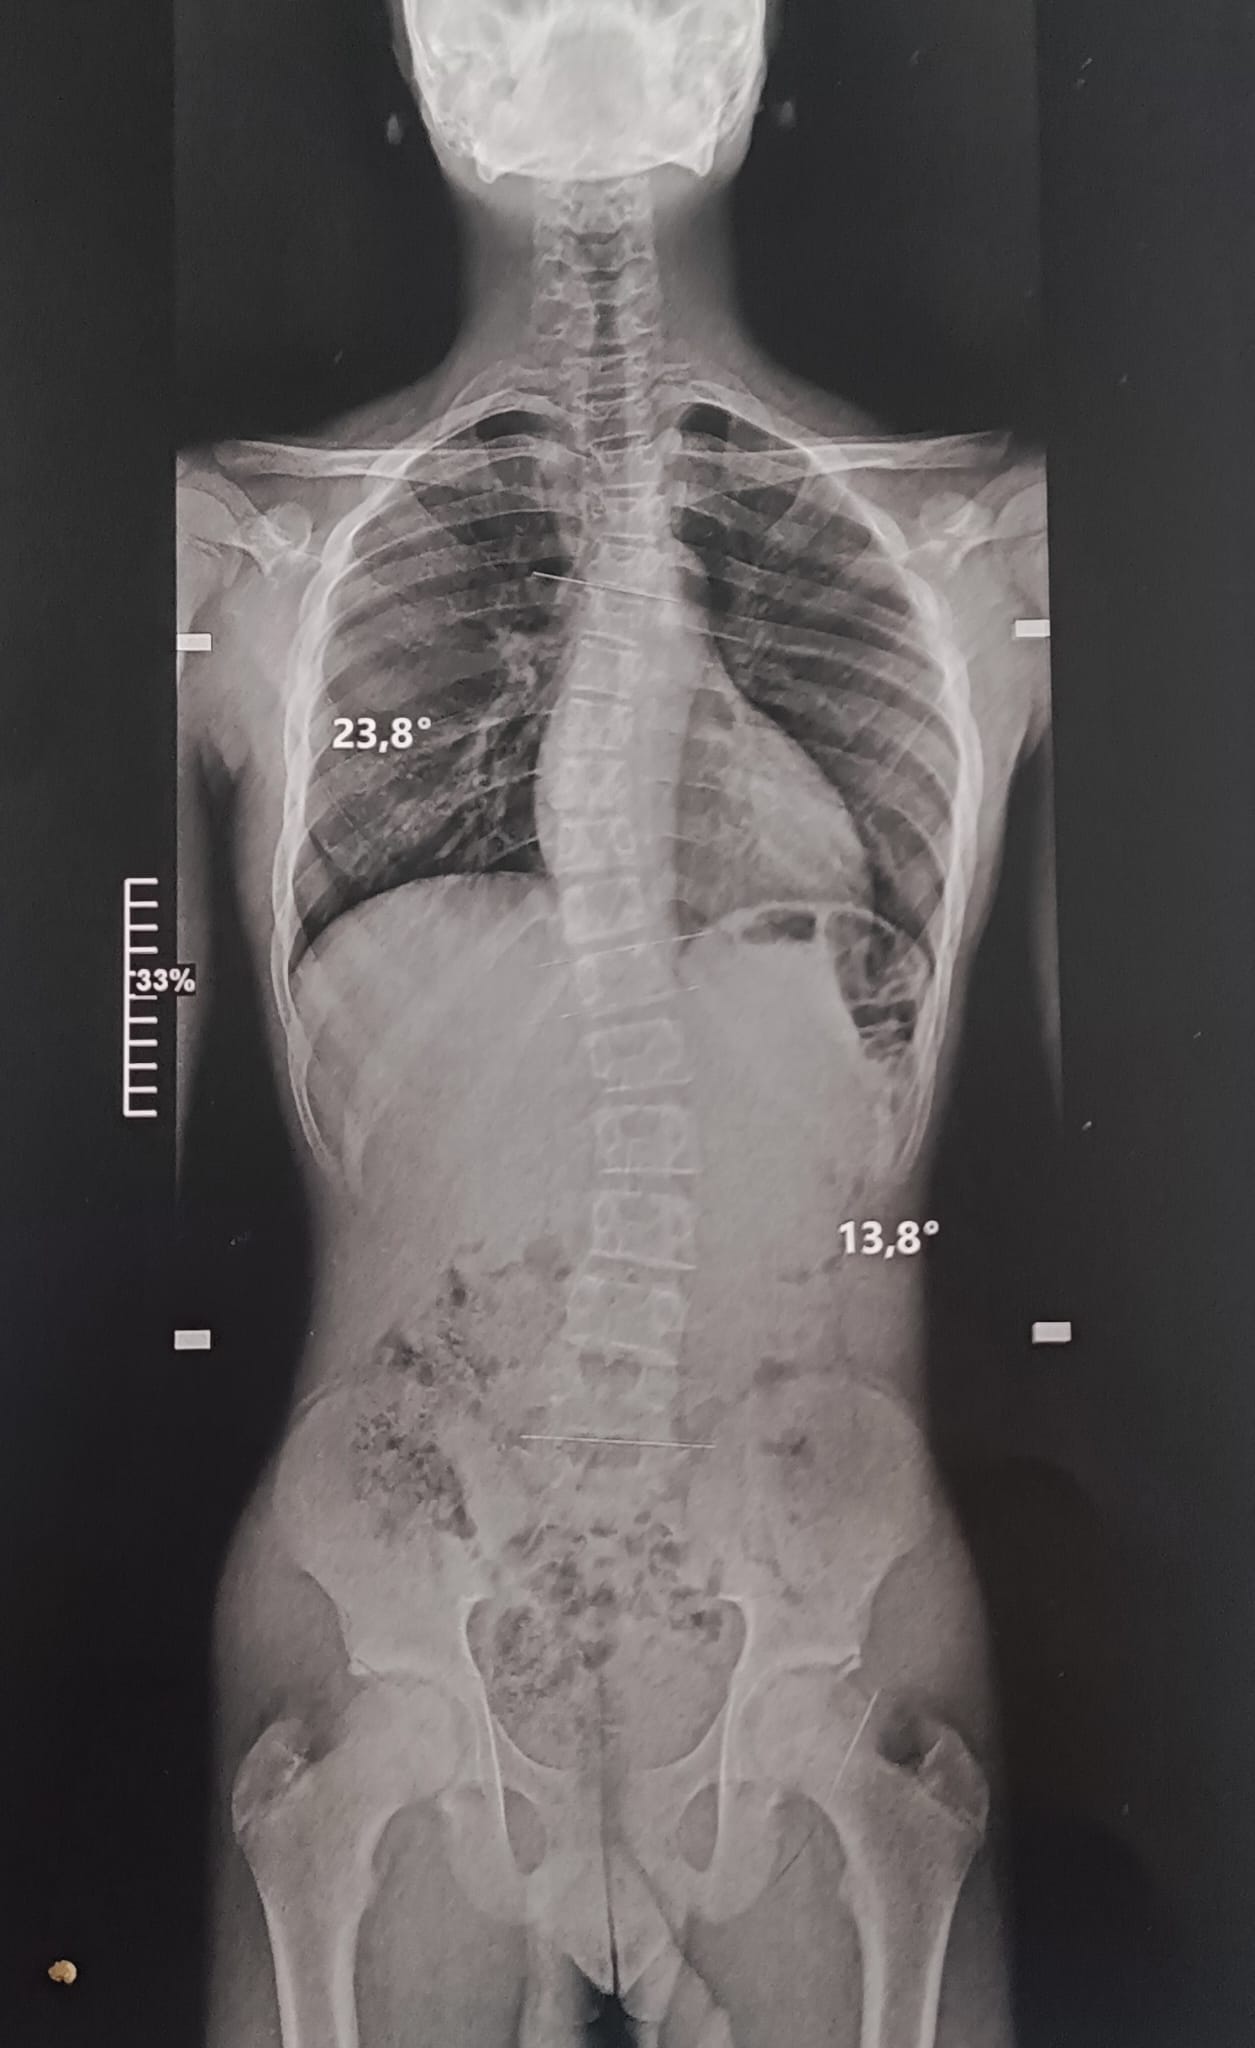

La scoliose est une déviation de la colonne vertébrale dans les 3 plans de l’espace. Celle-ci amène une silhouette asymétrique (visible au niveau des épaules et de la taille) et l’apparition de gibbosités (bosse), ainsi qu’un déséquilibre et une limitation de mouvement du tronc. Dans certains cas graves, la capacité respiratoire du patient peut se trouver limitée.

Le traitement se fait par appareillage au moyen d’un corset orthopédique sur mesure, moulé sur le corps et conçu de manière à permettre une croissance normale du rachis en corrigeant les déformations existantes.

Chaque corset est réalisé et adapté selon la morphologie du patient. Il tient compte de la déformation du rachis, du poids et de la taille de celui-ci, ainsi que de la prescription médicale. Selon la déformation du rachis et le modèle de corset prescrit, les temps de port de ce dernier peuvent être variables. De même des ajustements peuvent être réalisés selon l’évolution de la pathologie et de la morphologie du patient.